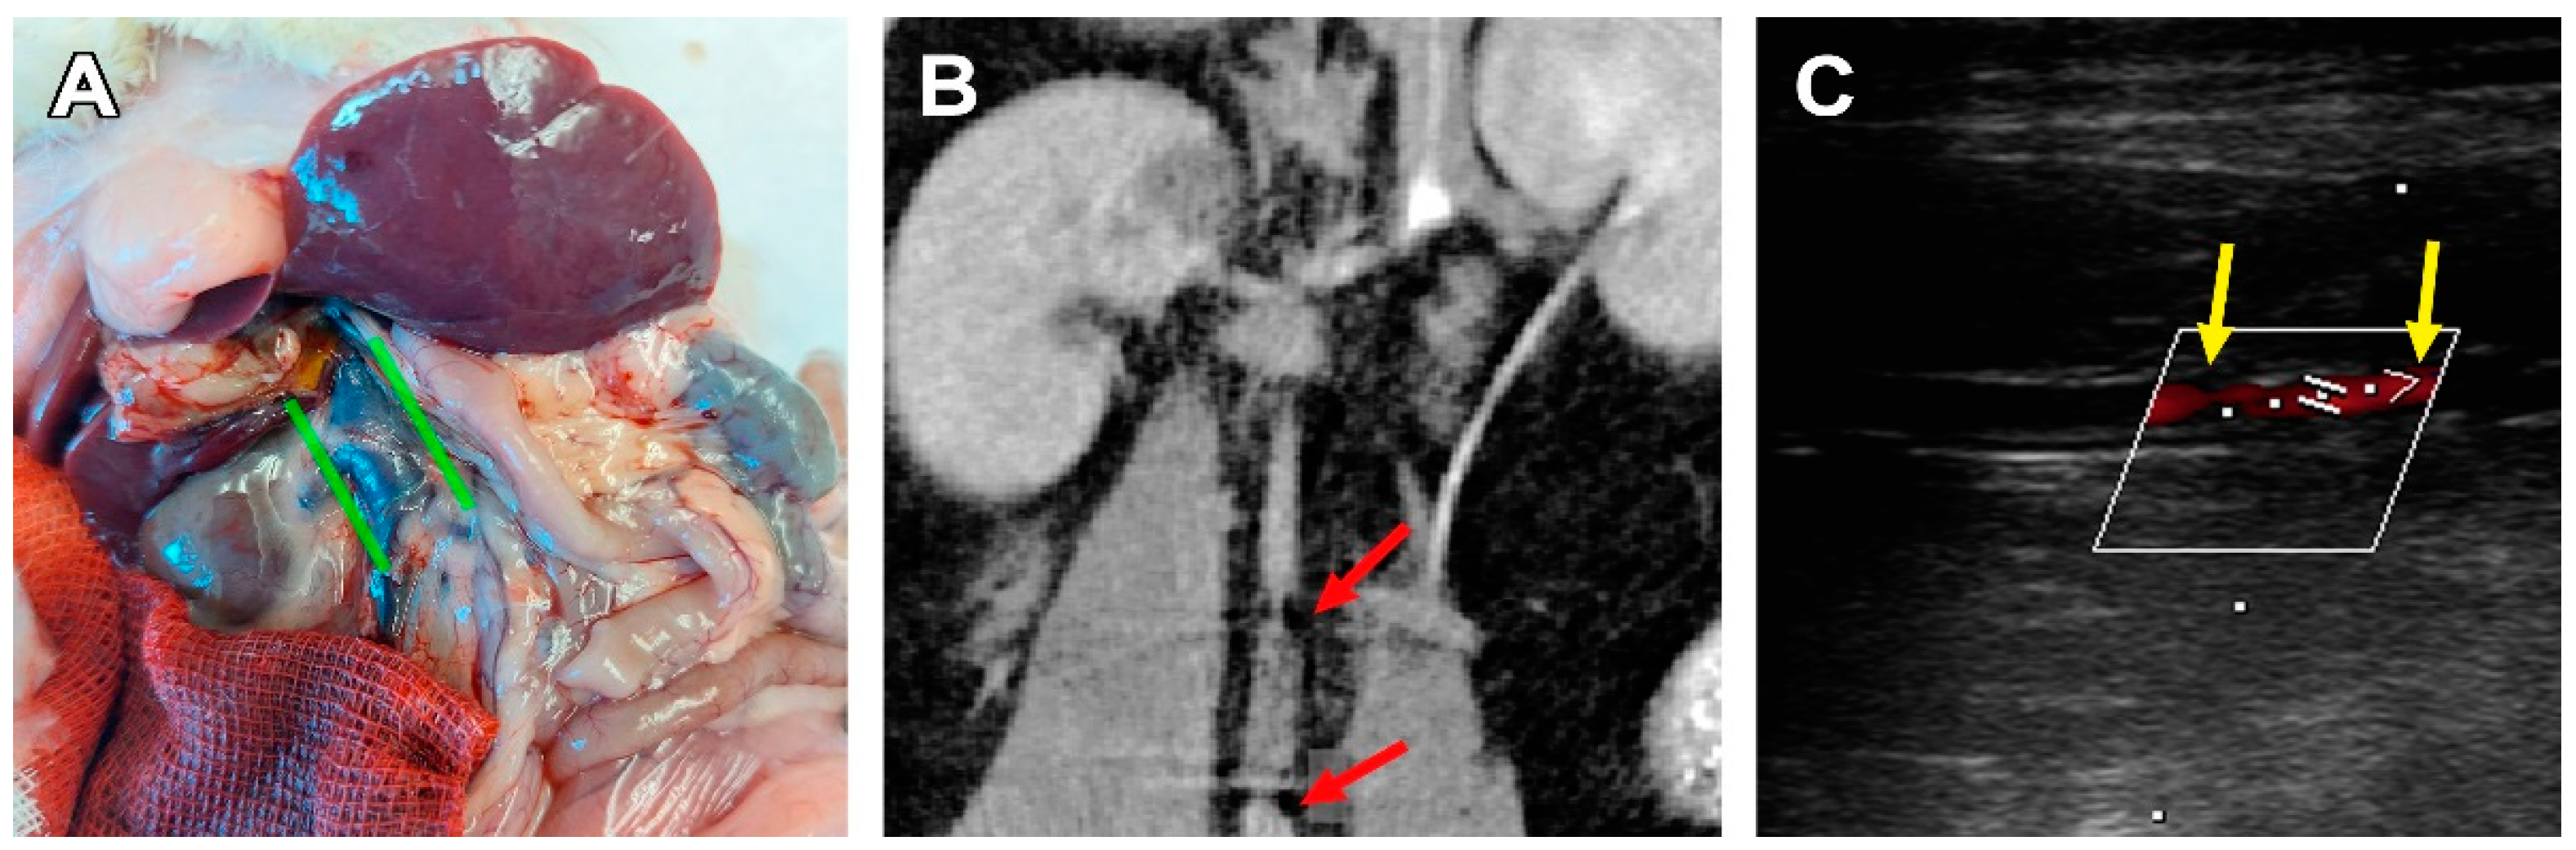

3.2. Surgical Outcomes

3.3. PCL Scaffold Transformation

4. Discussion